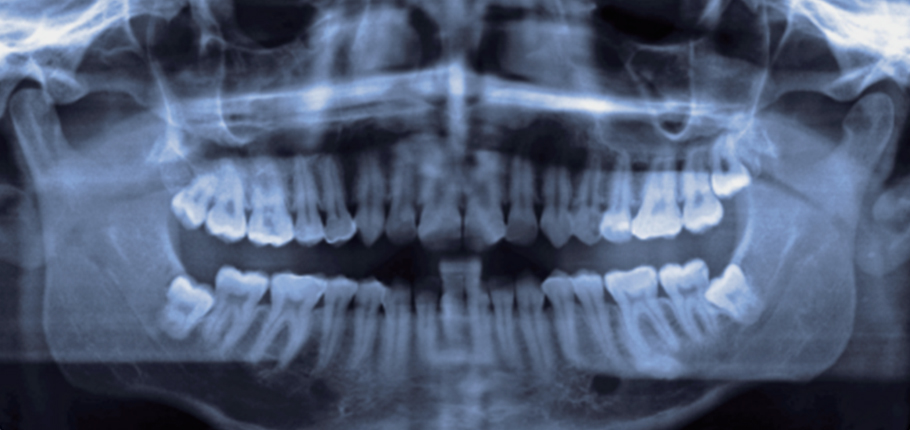

엑스레이 촬영

치아 뿌리 부근의 염증 주머니

다소 시간이 걸리더라도 발치 후 엑스레이 촬영 등을 통해 남아있는 염증을 파악 후 완벽하게 제거합니다.

발치 후 완벽하게 제거되지 못한 염증은 치근낭을 유발하여 발치 치아 주변 건강한 치아와 잇몸까지 염증을 유발하기 때문에 꼭 필요한 과정입니다.